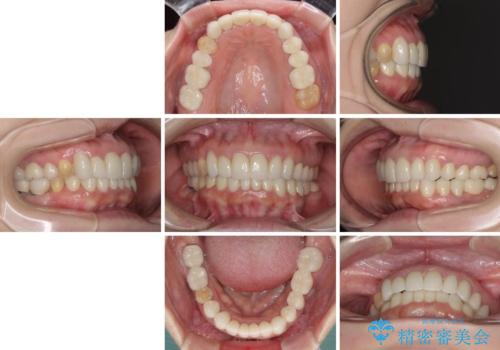

- 下顎の前歯に激痛を覚えて来院された患者様です。

取り急ぎ下顎前歯数歯の根管治療を、銀座しらゆり歯科医院長の林先生にお願いし、それ以外に気になっている、不自然な色調のクラウン、金属部分が見えてブラッシングがしにくいインプラント補綴、口元の突出感、出血のしやすい歯周ポケットなど、全てを解決するための治療を行うこととしました。

期間と費用はかかりましたが、気になっていた部分全てを改善でき、患者様には大変満足していただきました。